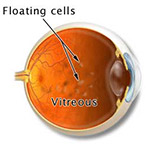

Flashes and Floaters

Tiny bits of vitreous gel or cells that cast shadows on the retina.